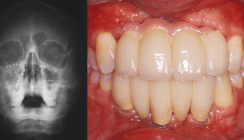

Inspiriert von der Bionik setzt Wolfgang Dinkelacker bei seinem Behandlungskonzept darauf, die Natur bestmöglich zu imitieren und Strukturen naturgetreu nachzubilden. Damit die Implantation gelingt, müssen die vorhandenen knöchernen Strukturen und die vorgesehene prothetische Versorgung in die Planung einbezogen werden.

Alle Arbeitsschritte werden samt der verwendeten Materialien Schritt für Schritt erklärt und durch Grafiken und Bilder visualisiert.